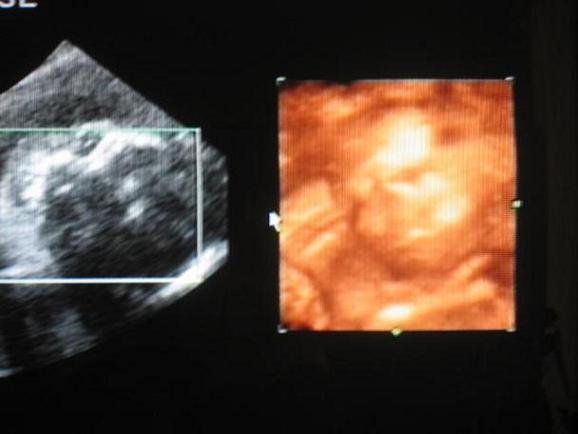

Nagyon szép Álmos, gyönyörű nevet választottatok! Nagyon bűbáj a kis pofija!!!

Na, már én is nagyon kíváncsi vagyok, Levi vagy Enikő lakik-e benn...akármi is, a Tied lesz, gyönyörű és imádni fogod!!